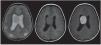

Los astrocitomas subependimarios también pueden identificarse como grandes masas intraventriculares heterogéneas que realzan poscontraste endovenoso (fig. 3).

Figura 3. Resonancia magnética, corte axial, de una paciente de 7 años de edad. Se observa una masa voluminosa intraventricular, ovoidea y sólida, ubicada en el ventrículo lateral derecho. Es hiperintensa en ponderación T2, isointensa en ponderación T1 y realza en forma significativa luego de la administración del contraste paramagnético. La imagen resulta compatible con un astrocitoma subependimario de células gigantes.